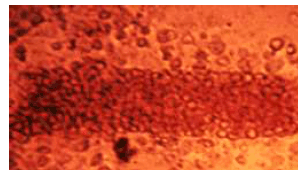

A figura a seguir mostra cristais de fosfato de cálcio, observados no sedimento urinário. Tal achado é comum na síndrome nefrótica.